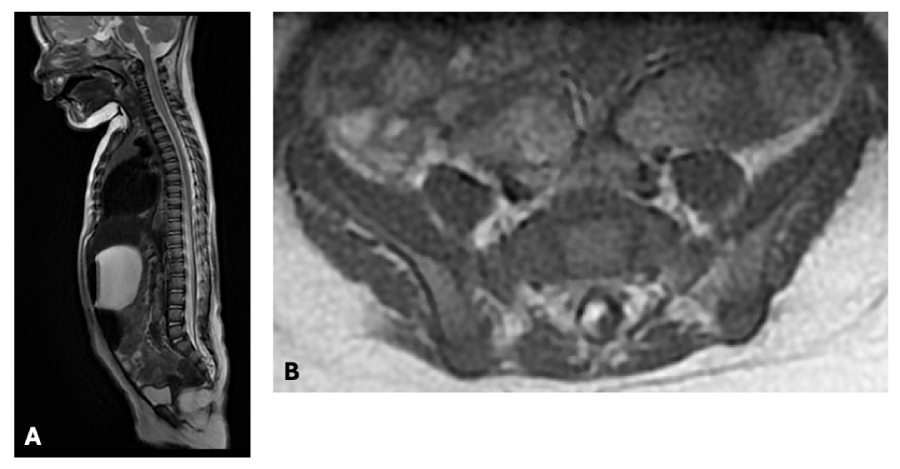

A 5-month-old baby girl was referred to our center for assessment and management as a transitional lipoma had just been diagnosed. A few days after birth, erythema of the intergluteal folds and the vulva was noted and was initially diagnosed as nappy rash. A couple of weeks later, a diagnosis of angioma was made by a dermatologist and due to a deviation of the intergluteal fold, a spinal ultrasound was ordered. The spinal ultrasound demonstrated a low-lying cord with its extremity in continuity with a hypoechoic mass measuring 21 x 6 mm, primarily suggestive of a lipoma. Spinal MRI one month later confirmed the diagnosis of a conus lipoma. She was thus referred to our center soon after for management. At that time, she was asymptomatic. Her neurologic and orthopedic examinations were completely normal. Bladder and renal ultrasound was also normal. Repeat MRI, 6 months later, confirmed a transitional subtype of conus lipoma, predominantly located on the right anterolateral side from L4 to S5 with an associated low-lying cord which termination is poorly defined around S2, without syringomyelia. As she was completely asymptomatic, a shared decision was made with the parents to opt for clinical assessment every 6 months.

Figure 1: Initial radiological presentation at 7 months of age of an anterolateral trans dural transitional conus lipoma A: Sagittal T2 B: Axial T1 View Figure 1